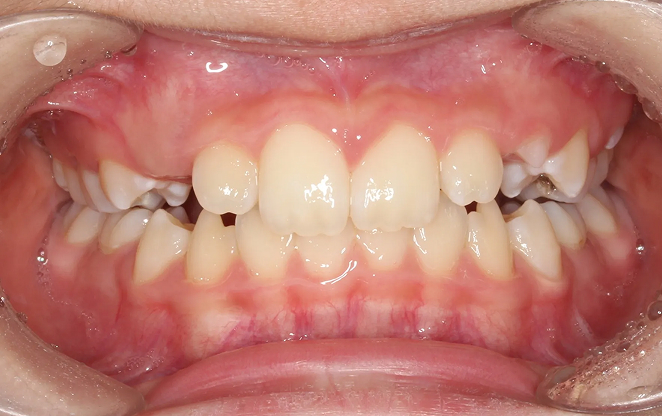

Before

After